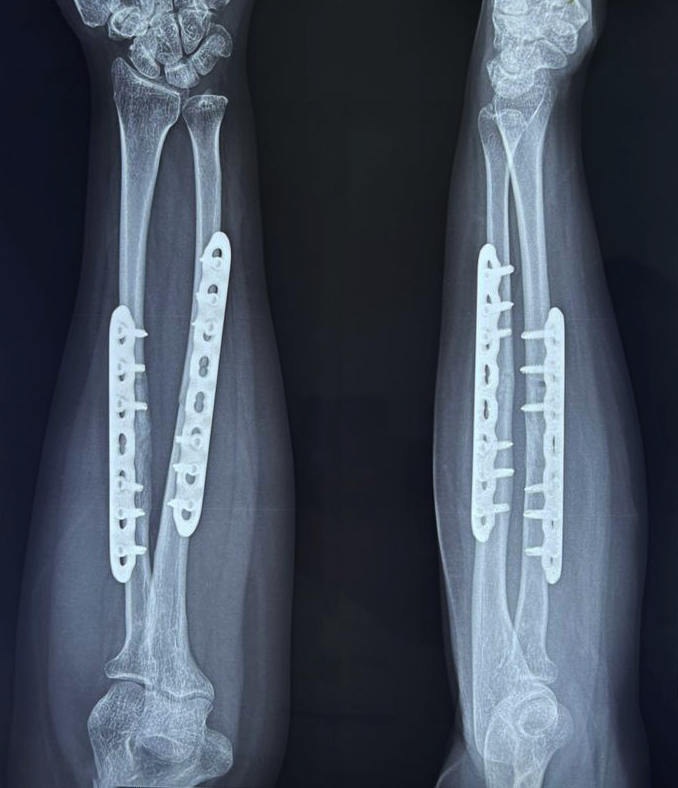

- Fracture Treatment: We specialize in the surgical and non-surgical treatment of

fractures, utilizing advanced techniques to ensure optimal healing and recovery.

- Expertise in Trauma Care: Dr. Zambare is highly skilled in managing complex trauma

cases, including multi-limb injuries and severe fractures. His expertise ensures that patients receive

precise and effective treatment for their injuries.

- Imaging and Diagnostic Services: We offer comprehensive imaging and diagnostic

services, including high-resolution X-rays and orthoscannograms, to accurately diagnose and plan

treatment for orthopaedic conditions.